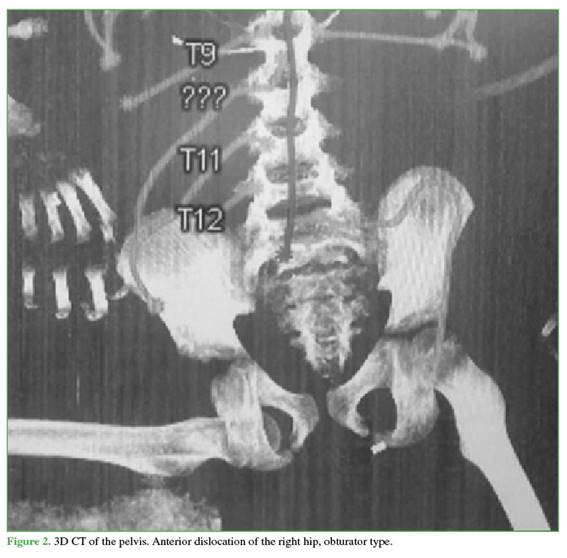

Orotracheal intubation was performed. A cranial CT scan showed an epidural hematoma and a frontotemporal fracture without surgical indication. Initial pelvic CT revealed right hip joint incongruity consistent with an anterior dislocation of obturator type (Figure 2); associated injuries were ruled out.

CT was useful to confirm the dislocation direction, although it is not ideal for detecting acetabular fractures in children due to unossified cartilage; MRI would be more appropriate,8 but was not performed. This case corresponded to an isolated dislocation (grade I),10 without associated injuries, which is common in children under 8 years of age, in whom acetabular fractures are rare.14 Chondral and osseous injuries increase with age.3